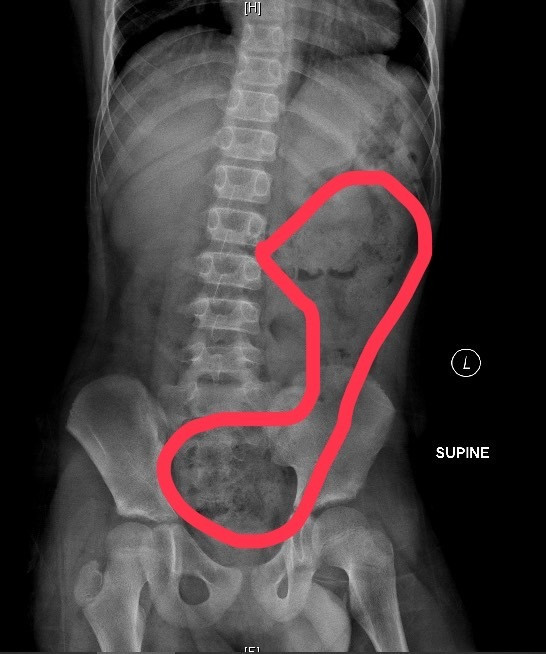

一名高雄11歲男童日前腹痛難耐、冒冷汗、嘴唇發紫,送醫檢查後竟被發現,腸道裡塞滿糞便,積糞甚至「快到胸口位置」。經灌腸後才順利排出大量糞便。醫師診斷為嚴重功能性便秘,而元凶正是許多孩子都有的壞習慣:上廁所滑手機。

▲11歲男孩腹部X光片,圖上紅圈範圍為便便堆積的地方/阮綜合醫院提供